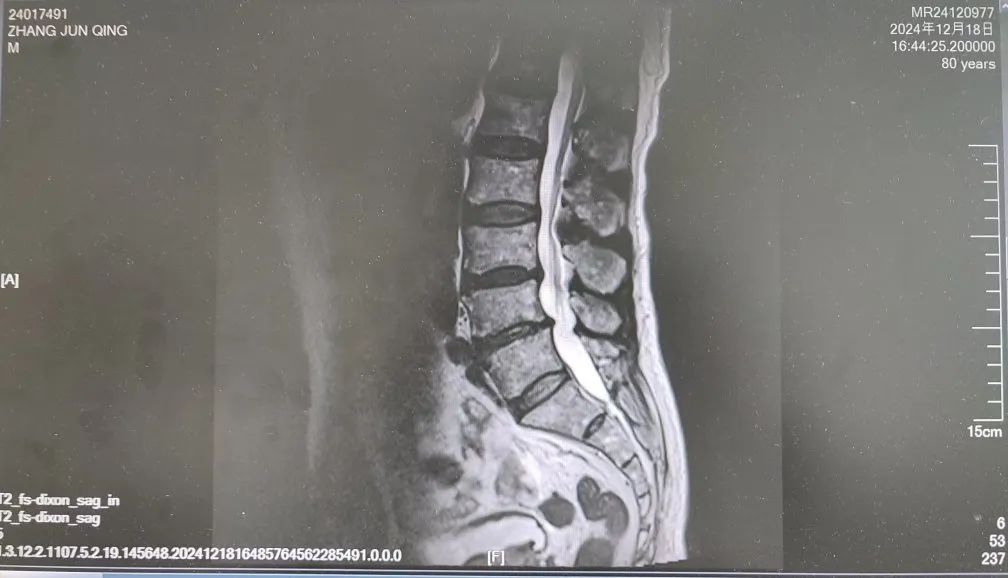

內(nèi)容提要 很多人都想擁有纖細(xì)、健美的雙腿,嘗試多種健身方法,效果卻始終不理想。然而社會(huì)上大約有萬分之四的人,他們不用減肥,雙腿就會(huì)慢慢“瘦”下來,如倒置的香檳酒瓶,醫(yī)學(xué)中稱之為“鶴腿”。不過這并非自愿,而是源于一種名為“腓骨肌萎縮癥”的罕見疾病。近日,市二院神經(jīng)內(nèi)二科趙智江主任團(tuán)隊(duì)就幫助一位受腓骨肌萎縮癥困擾4年之久的患者明確了病因。 #01 “鶴腿”多年不明病因 竟是罕見病作祟 患者80歲,四年前無明顯誘因出現(xiàn)步態(tài)異常,行走困難,起初以為是勞累所致,并未過多在意。然而,近一年來癥狀逐漸加重,雙下肢膝關(guān)節(jié)以下麻木、發(fā)涼,行走時(shí)右下肢有甩腳動(dòng)作,呈跨閾步態(tài),右足趾背屈不能,同時(shí)存在站立不穩(wěn)、不能蹲下等癥狀,嚴(yán)重影響日常行走。這一年間,他輾轉(zhuǎn)市內(nèi)多家醫(yī)院,經(jīng)歷了無數(shù)次的檢查和咨詢,卻始終未能得到確切診斷。 近日,患者經(jīng)多方打聽,來到了以診治神經(jīng)疑難病為特色的市二院神經(jīng)內(nèi)二科。入院后,趙智江主任為患者進(jìn)行了細(xì)致入微的查體,發(fā)現(xiàn)患者雙側(cè)大腿下三分之一處及小腿肌肉萎縮。進(jìn)一步完善頭顱、頸椎及胸椎核磁的檢查,由于患者存在跨閾步態(tài),結(jié)合檢查結(jié)果,初步考慮為腓總神經(jīng)麻痹。 頭顱、頸椎核磁回報(bào)后,基本上排除了神經(jīng)根的疾病和脊髓疾病。肌電圖結(jié)果提示四肢周圍神經(jīng)受累,右側(cè)腓總神經(jīng)損傷更重,修正診斷為周圍神經(jīng)病。然而,周圍神經(jīng)病存在多種病因,需進(jìn)一步查找病因。趙智江主任結(jié)合患者雙下肢肌肉萎縮情況,排除其它病因?qū)е碌闹車窠?jīng)病,最終明確診斷為腓骨肌萎縮癥。 頭顱核磁影像 頸椎及腰椎核磁影像 隨后,中國醫(yī)科大學(xué)附屬第一醫(yī)院神經(jīng)內(nèi)科著名專家何志義教授及遼寧名醫(yī)、市二院卒中中心主任閔連秋教授在查房時(shí)同樣肯定了腓骨肌萎縮癥的診斷。 腓骨肌萎縮癥是一組具有高度臨床和遺傳異質(zhì)性的周圍神經(jīng)單基因遺傳病,以慢性進(jìn)行性四肢遠(yuǎn)端肌無力肌萎縮、末梢型感覺障礙、腱反射減退或消失和高弓足等骨骼畸形為主要臨床特征,多為兒童和青少年期起病。該患者老年起病,極為罕見!目前,腓骨肌萎縮癥無特效治療藥物,主要以支持治療為主。今后,患者只要在康復(fù)醫(yī)師的指導(dǎo)下,根據(jù)神經(jīng)損害范圍進(jìn)行合理的康復(fù)鍛煉,就能保持較好的活動(dòng)能力,提高生活質(zhì)量。 市二院神經(jīng)內(nèi)二科趙智江主任團(tuán)隊(duì)擁有豐富的神經(jīng)系統(tǒng)疑難疾病診治能力,曾幫助大量飽受罕見病困擾多年的患者明確了診斷。隨著診療水平的持續(xù)精進(jìn),神經(jīng)內(nèi)二科將為更多患者提供精確診斷及治療,為更多的神經(jīng)疑難疾病明確診斷,為患者帶來福音。 #02 人民醫(yī)院 人民名醫(yī) 趙智江 主任醫(yī)師 副教授 ·葫蘆島市第二人民醫(yī)院神經(jīng)內(nèi)二科主任 ·中國卒中學(xué)會(huì)高級(jí)會(huì)員 ·中國老年保健醫(yī)學(xué)研究會(huì)老年腦血管病分會(huì)委員 ·北京神經(jīng)內(nèi)科學(xué)會(huì)腦小血管病學(xué)會(huì)委員 ·安徽醫(yī)藥雜志審稿專家 專業(yè)特色:以腦血管病為核心研究方向,擅長各類神經(jīng)系統(tǒng)疾病的診療,尤其在腦血管病、帕金森綜合征、頭暈、頭痛、癲癇、重癥肌無力以及中樞神經(jīng)系統(tǒng)脫髓鞘等神經(jīng)系統(tǒng)疑難、危重疾病的診療方面積累了豐富的臨床經(jīng)驗(yàn)。主持多項(xiàng)重要科研項(xiàng)目,并將最新的科研成果應(yīng)用于臨床實(shí)踐,撰寫十余篇論文著作。